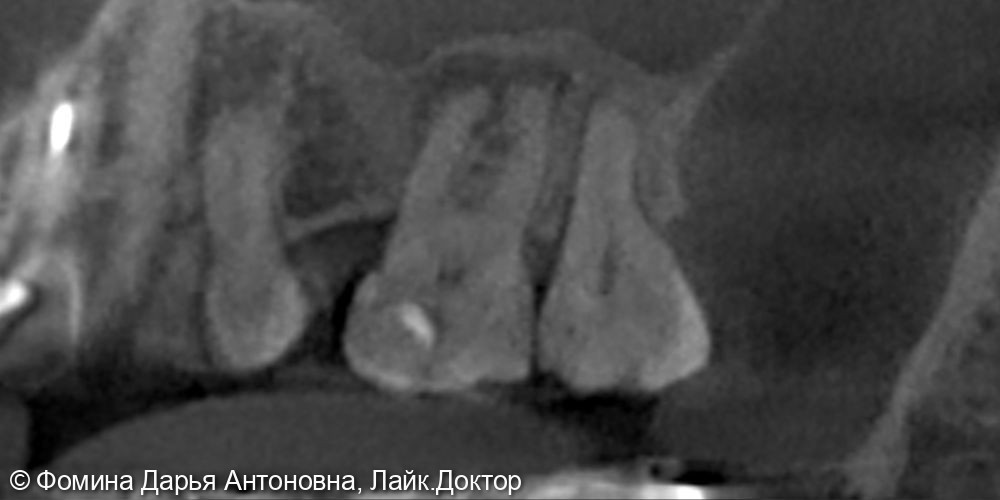

Зуб был пролечен около 5 лет назад в другой клинике и клинически не беспокоил. Однако при проведении КЛКТ выявили периапикальный очаг воспаления — скрытую инфекцию у верхушки корня.

Диагностика с помощью 3D-КТ: источник боли был обнаружен в 16 зубе – воспаление на верхушках корней. Зуб ранее лечили от кариеса более 5 лет назад.